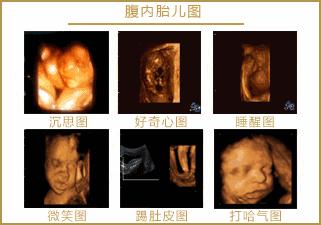

孕期B超检查可以诊断出宝宝的生长发育是否正常、有没有畸形、胎盘的位置是否适合自然分娩等情况。但是,准妈妈在整个孕期应该做几次B超?阴道B超是否会导致流产?B超检查结果绝对可靠吗?它是否对胎儿足够安全?《健康加油站--人口直通车》邀请北京世纪坛医院超声科主任、主任医师 杨敏带您一起来了解一下孕期超声那些事儿。

4 孕期超声一般会有六次

第一次超声检查:6-8周期间:

主要是观察是否为宫内孕,是单胎或多胎,是否有胎心,胎芽长度,主要为建档提供参考,需憋尿检查。

第二次超声检查:11-14周期间

主要为测量胎儿NT值。

第三次超声检查:22-24周期间

本次检查主要为检测胎儿是否患有重大畸形,主要是筛查出胎儿致死性畸形:无脑儿、严重脑膨出、严重开放性脊柱裂、单腔心等;

第四次超声检查:28-33周期间

晚孕期胎儿畸形筛查

第五次超声检查:36-38周期间

这个时候检查主要是了解胎儿生长发育情况,确定胎位、看胎儿大小、了解胎盘成熟度,看看羊水脐带的情况,进行产前的最后评估,为胎儿生产做好准备。

第六次超声检查:生产前最后检查